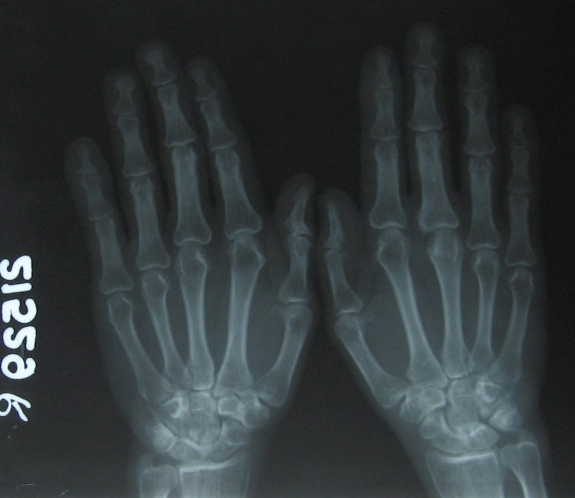

Psoriasis early hand